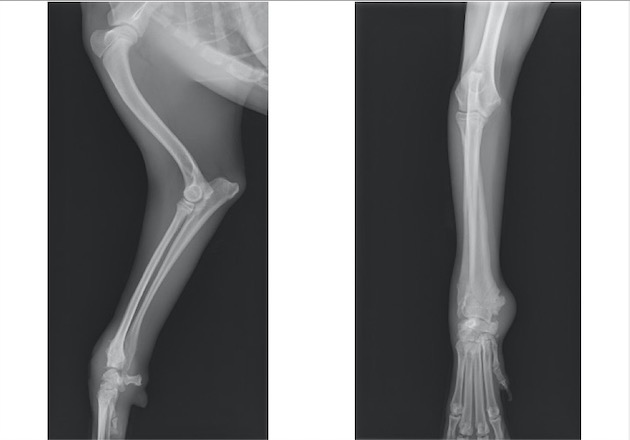

トイプードル 雌 3ヵ月齢

ソファーの背もたれから落下後、右前肢居城を主訴に来院。

両前肢の明らかな左右差は認められませんでしたが、触診検査において右側肘関節における圧痛を確認しました。

単純X線検査を実施したところ、上腕骨遠位外顆骨折が認められ、上腕骨遠位の成長板をまたぐ骨折であったことから成長板骨折(Salter-Haris Type4)と診断して外科的処置を実施しました。

背掌像より上腕骨遠位外顆の骨折が認められました